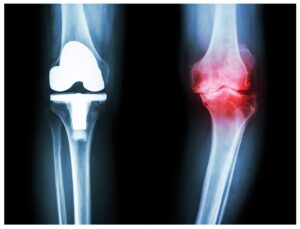

כאבים במפרקים של הברכיים

בכל פעם שאתה מבחין בכאב חריג בברכיים שלך

או מבחין ברעש צריבה במהלך תנועת הברך שלך,

עליך לשקול לבדוק אם מדובר בכאבים במפרקים או לא.

סביר יותר להניח שזו אי נוחות בדלקת פרקים

שדי ברורה מהנפיחות או האדמומיות על הברכיים.

במקרה כזה, תרגישו חוסר יציבות ונוקשות בברכיים.

כתוצאה מכך, יהיה לך קשה ליישר את הברכיים

או להזיז אותן בקלות כמו קודם.